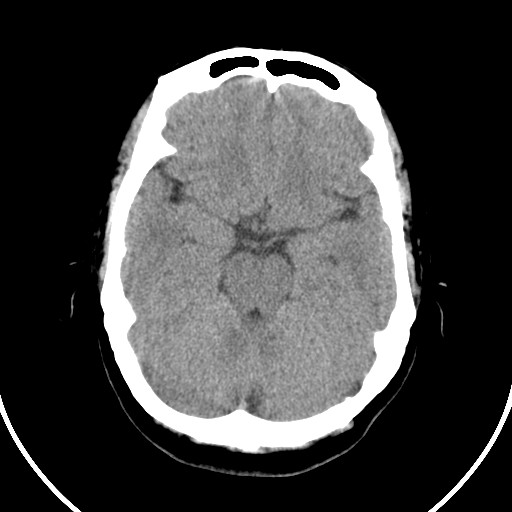

标题: CT21850:女,56岁,右中指淤肿,右手麻痹1天

女,56岁,右中指淤肿,右手麻痹1天

右侧基底节多发小梗塞

右基底结区腔梗

右侧基底节区腔隙性脑梗塞

右侧基底节多发腔梗!

双侧侧脑室额角旁对称性略低密度影,边缘模糊,无占位效应,考虑轻度脑白质稀疏症(病人有高血压吗).,右枕叶低密度影多为伪影,不放心薄扫一下.

考虑脑白质病。

考虑脑白质病

右枕叶条状低密度影不应该忽略可能极具意义